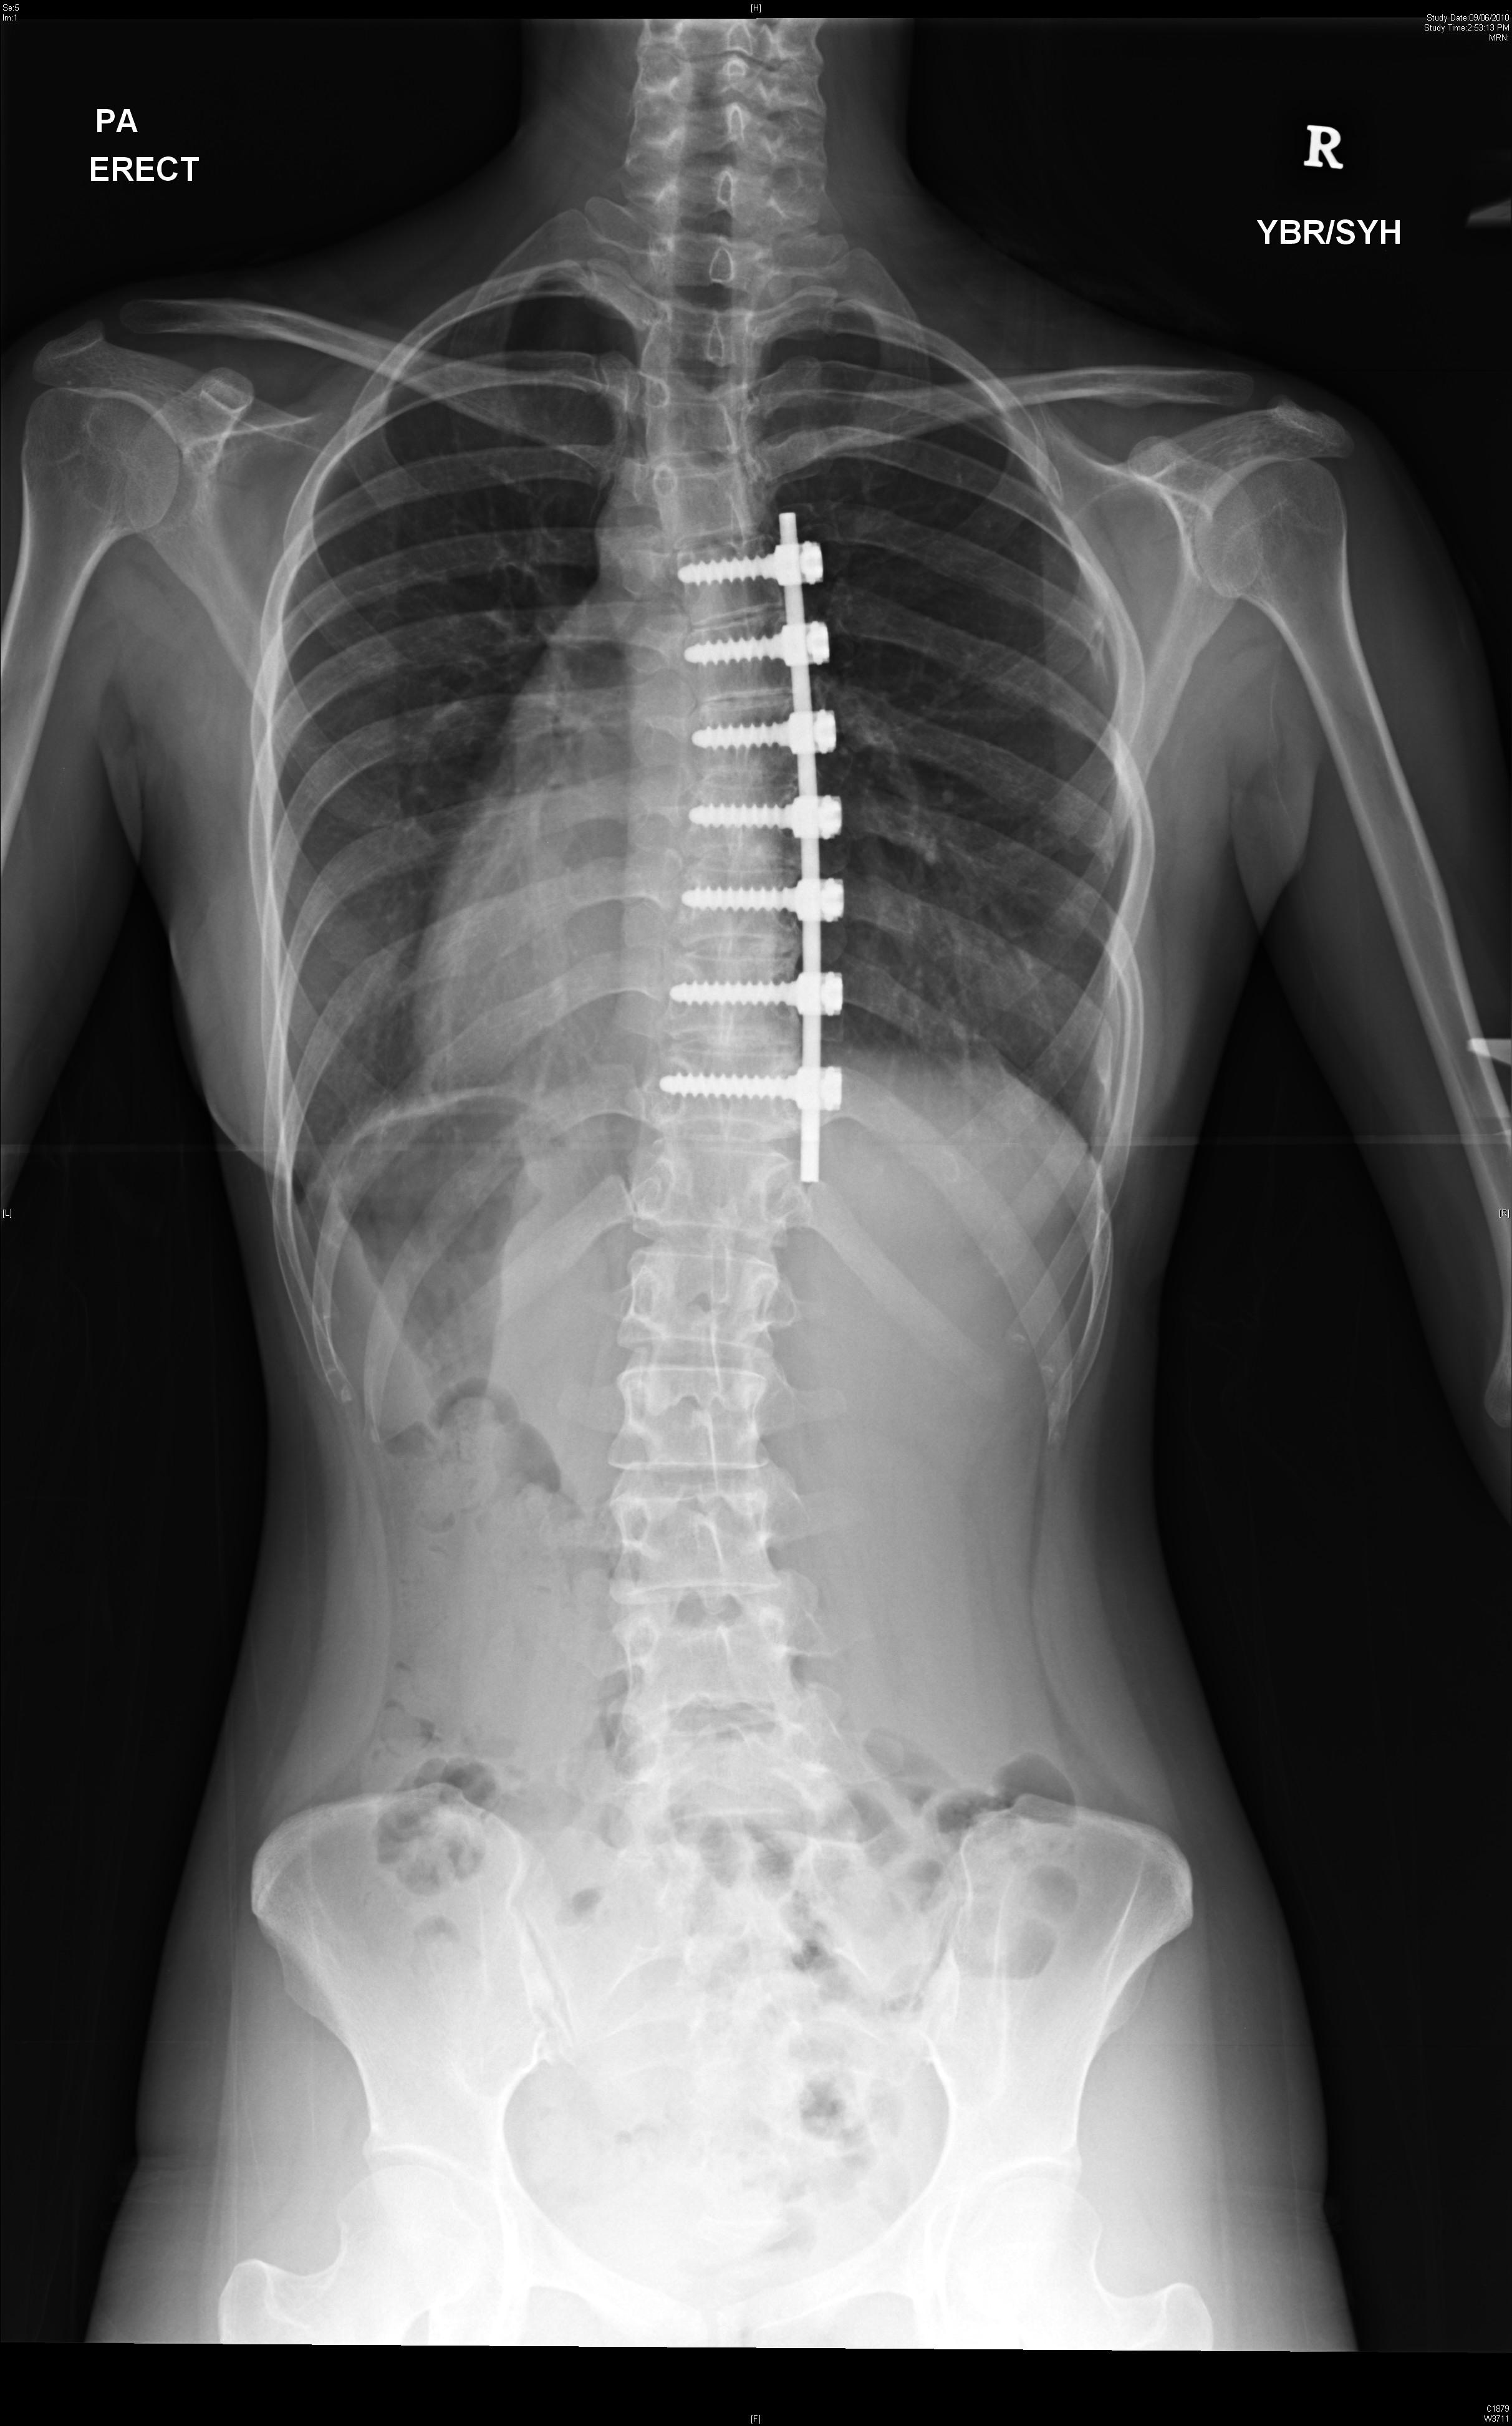

The thyroid gland is prone to developing small lumps within it which are called nodules. These may appear gradually or suddenly. Occasionally they may be painful. Figure 1 shows a gland with several large nodules – a common condition known as multinodular goitre. About 60% of women will have a thyroid nodule present if they were to have

an ultrasound scan of the neck. The vast majority of these nodules

are benign but may require treatment if they cause swallowing or breathing problems. However, 5-10% of nodules may harbour a cancer and therefore require surgical removal. Trying to decide which 200-101 nodules are sinister is challenging.

Figure 1: A large 15 cm multinodular goitre removed from a patient. This had no cancer in it but caused swallowing difficulties